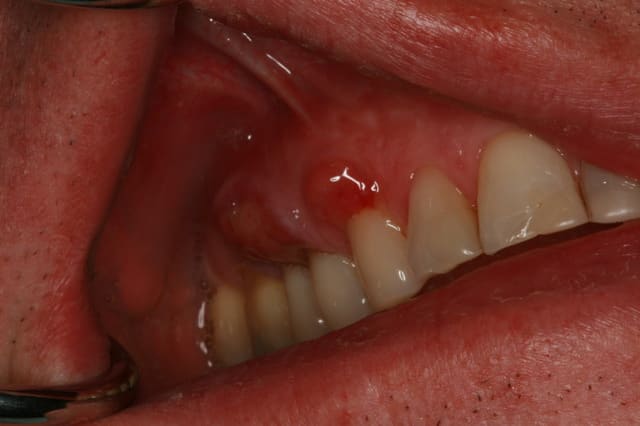

A la vue de ta photo on peut comprendre que tu as choisi de faire une tunnelisation. En ayant fait plusieurs dizaines et pu les comparer avec les lambeaux déplacés coronairement traditionnels ou modifiés, je ne suis pas sûr que le résultat esthétique soit meilleur : je n'aime pas la partie exposée du greffon conjonctif qui a esthetiquement souvent du mal a s'intégrer harmonieusement dans le contexte gingival du site receveur.

En post op, le lambeau tunnel revouvrait entièrement le greffon, Je crois que l'épaisseur du greffon a favorisé une nécrose de surface du lambeau, de plus quelques points ont cédées avant le contrôle de 2 semaines